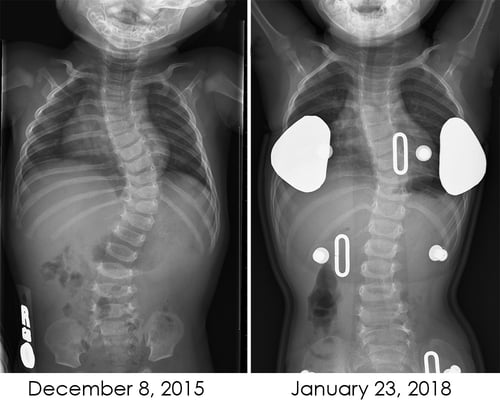

X-rays of torsoInstead of taking physical measurements, children are scanned using a handheld computer-assisted design (CAD) laser, which creates a digital 3D framework of the child’s body. The scan takes less than a minute to complete. Children younger than about 4 are still usually put under general anesthesia for 3D measurement and scanning. But older, more compliant children who are able to stand still remain awake while the measurements are taken in a clinic room.

Now, two years — and 4 casts and 3 braces — later, Odehn is making incredible progress. The curvature of his spine has gone from 57 degrees to 34 degrees (27 while wearing the brace).